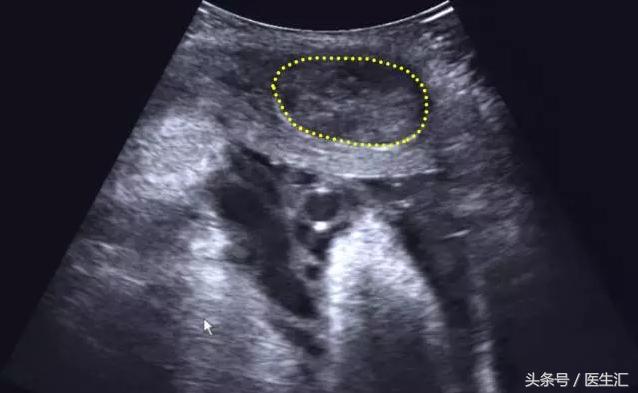

2.子宫肌瘤:位于肌层内,边缘较清,形态规则,向宫腔内或宫外突出。(见图3黄色圈内)

图3,孕妇子宫壁见多个低回声团,最大一个位于右前壁,大小约:40mm×26mm,边界清,内部回声分布均匀。